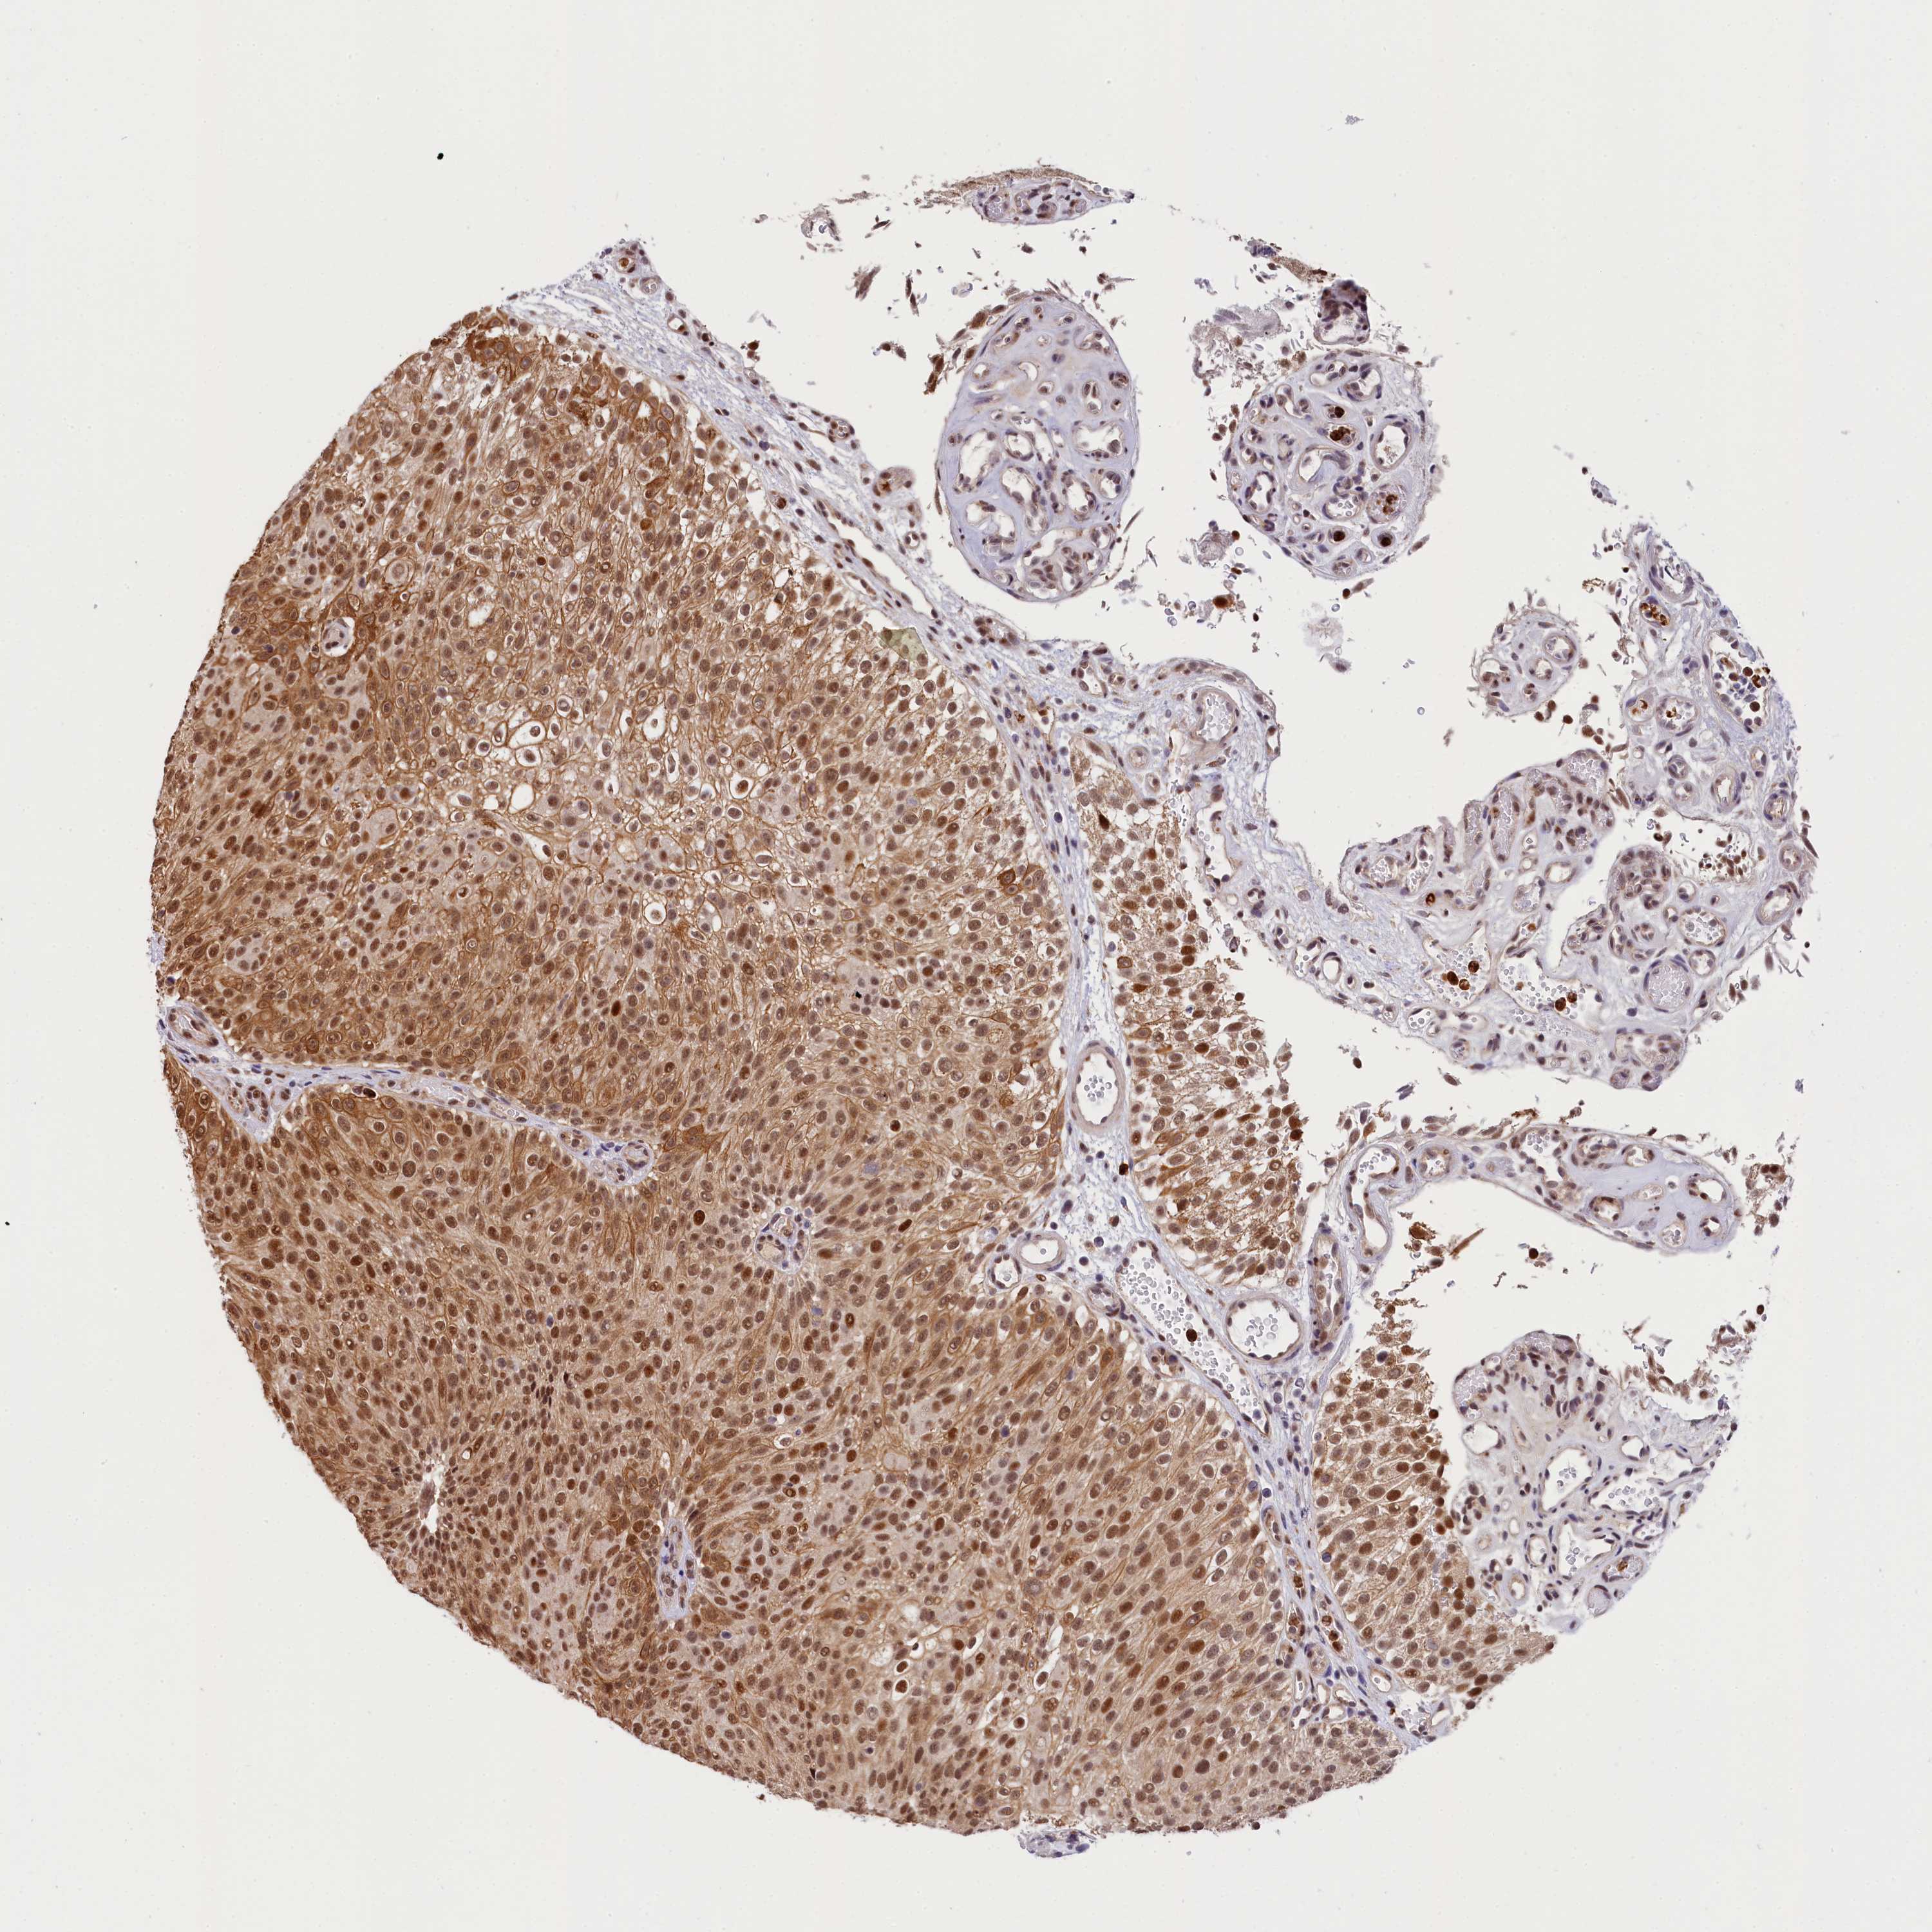

UROTHELIAL CANCER - Protein expressioni

A mouse-over function shows sample information and annotation data. Click on an image to view it in a full screen mode. Samples can be filtered based on level of antibody staining by selecting one or several of the following categories: high, medium, low and not detected. The assay and annotation is described here.

Note that samples used for immunohistochemistry by the Human Protein Atlas do not correspond to samples in the TCGA dataset.

Antibody stainingi

Antibody staining in the annotated cell types in the current human tissue is reported as not detected, low, medium, or high, based on conventional immunohistochemistry profiling in selected tissues. This score is based on the combination of the staining intensity and fraction of stained cells.

Each image is clickable and will lead to virtual microscopy that enables deeper exploration of all samples and also displays staining intensity scores, fraction scores and subcellular localization as well as patient and tissue information for each sample.

Antibody HPA041124

Staining

High

Medium

Low

Not detected

Intensity

Strong

Moderate

Weak

Negative

Quantity

>75%

75%-25%

<25%

None

Location

Nuclear

Cytoplasmic/membranous

Cytoplasmic/membranous,nuclear

Urothelial carcinoma, High grade

Urothelial carcinoma, Low grade

Urothelial carcinoma, NOS